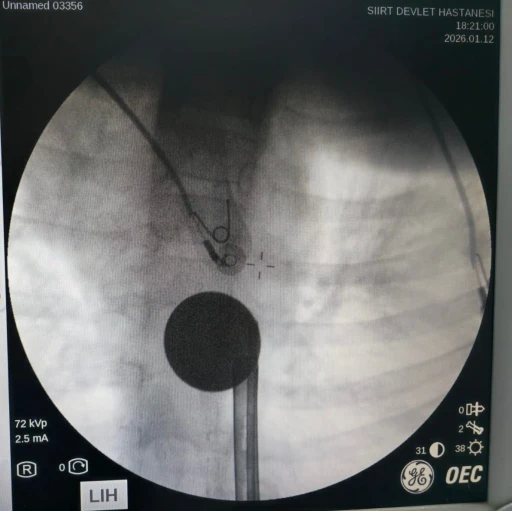

Medicana Bursa Hastanesi’nde Da Vinci Robotik Cerrahi Sistemi kullanılarak ilk cerrahi operasyon yapıldı. Operasyonun tamamlanmasıyla birlikte hastanede robotik cerrahi uygulamaları başlamış oldu. Medicana Bursa Hastanesi Üroloji Bölümü’nden Doç. Dr. Ahmet Şahan, yaptığı operasyonu değerlendirerek, "Robotik cerrahi sistemler, Genel Cerrahi, Göğüs Cerrahisi Kalp Damar Cerrahisi ve Jinekoloji alanlarının yanında Üroloji branşında da kullanılmaktadır. Hastanedeki ilk robotik cerrahi ameliyatı üroloji branşında prostat kanseri tedavisi ile başladı. 63 yaşındaki hastamıza uyguladığımız cerrahi operasyonla, hastamız sağlığına kavuştu " dedi.

Doç. Dr. Ahmet Şahan, Medicana Bursa Hastanesi’nde ilk olarak üroloji alanında prostat kanseri ameliyatının robotik cerrahi sistemle gerçekleştirildiğini kaydederken, "Hastamızın ilk yapılan tetkiklerinde PSA yüksekliği tespit edilmişti. Sonrasında kendisine biyopsi uygulandı ve prostat kanseri teşhisi konuldu. Hastamız, robotik cerrahi ile tedaviyi tercih etti. Operasyondan sonra yapılan kontrollerle birlikte hastamız bu operasyon sayesinde prostat kanserine ‘Elveda’ demiş oldu" şeklinde konuştu.

Prostat kanseri teşhisi aldığını ve araştırmaları sonucunda Doç. Dr. Ahmet Şahan’a ulaştığını belirten 63 yaşındaki Teoman Çetin Bilgin ise, "Sıkıntılarım artınca yapılan tetkikler ve biyopsi sonucunda ameliyat olmama karar verildi. Robotik cerrahinin daha hassas bir yöntem olması nedeniyle benim için daha uygun olabileceğini düşündük. Bu süreçte Doç. Dr. Ahmet Şahan, ameliyatın kendi hastanelerinde robotik cerrahi ile yapılabileceğini söyledi. Operasyon sonucunda da alınan patolojim temiz çıktı, prostat kanserini yendim" diye görüş verdi.